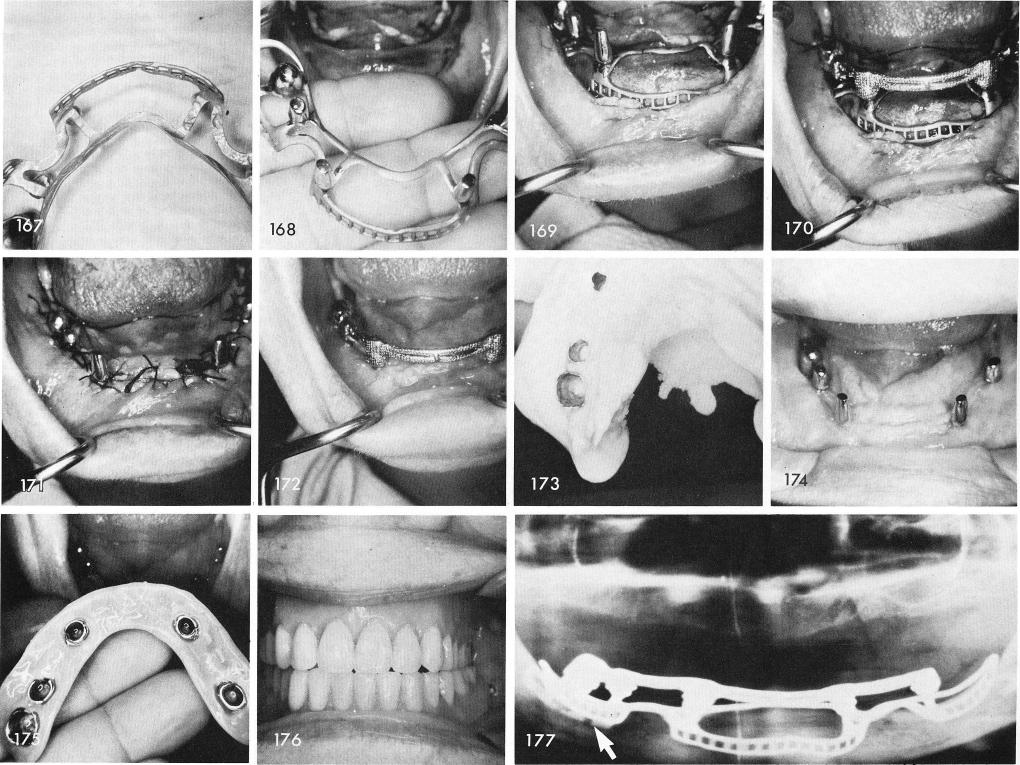

over the blade post, figs. 167, 168, 169, 170, 171. The superstructure was placed over the subperiosteal implant posts and the blade post, fig. 172, and pulled off with an alginate impression to obtain an accurate impression of the soft tissues, fig. 173. The tissues healed uneventfully, fig. 174, and the implant denture having five clasps rather than four was snapped into position, figs. 175, 176. The x-ray reveals the blade on the right side and the implant coping over it, fig. 177.

1 Casting framework with coping cemented over mandibular blade post